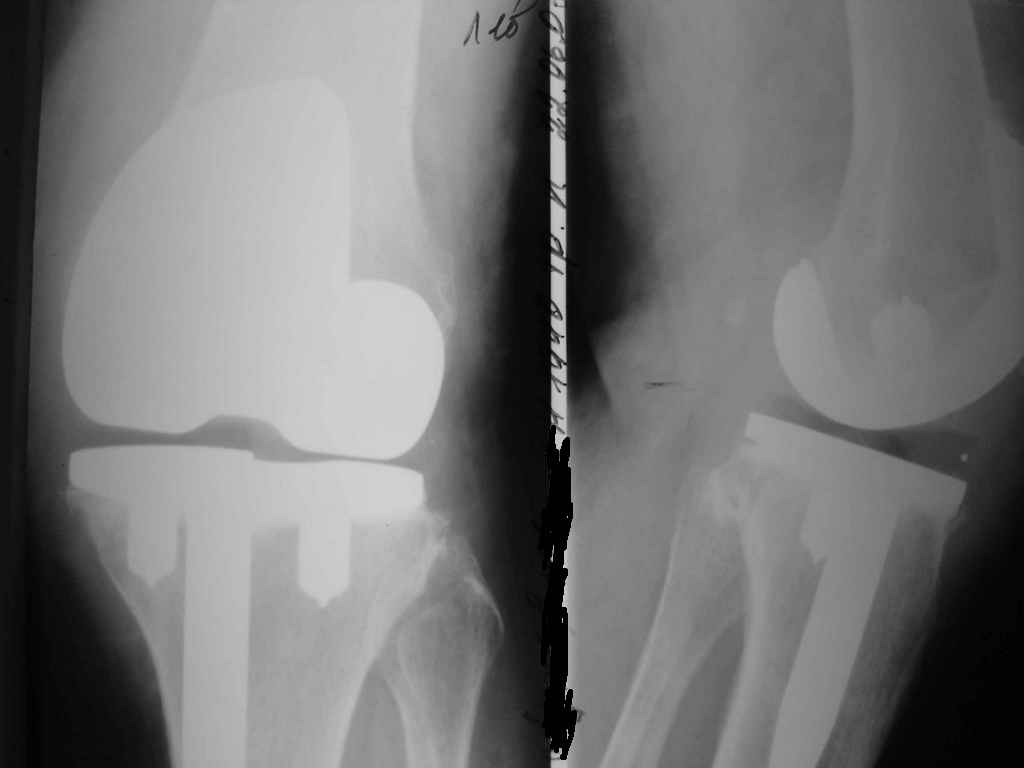

Уважаемые коллеги. Пациентка 65 лет соматически сохранна 6,5 месяцев назад выполнено замещениеколенного сустава интегральным эндопротезом Фримана Самуэльссона - цемент, по поводу ДОА. Послеоперационное течение с длительным субфебрилитетом. Местно без особенностей и выписана домой на 28 сутки с обьемом движений в колене 90 град. с частичной опорой. Дома отмечала субфебрильную лихорадку. Живет в небольшом поселке далеко от цивилизации. Контрольный осмотр в 3 месяца особых клинических проблем лечащий врач не нашел. Однако рентгенологически отмечены зоны остеопороза вокруг компонентов, на которые не обратил внимание. С 4 месяца отметила ухудшение - отек в колене, ограничение движений и боль. Лечилась у местного врача-хирурга (нестероиды и местно мазилки) - без эффекта. Обратилась только в 6,5 мес. Движения в суставе 20 град, отечность колена, выпот по УЗИ. Боль неопределенная, ходит с тростью. Лихорадки нет, в ан крови СОЭ 36 остальное норма, острофазовые тесты СРР повышен вдвое = 12 (при норме 6) Ревмотест - норма..Пункция - посев - роста не дает. Пробовали артроскопию - артрофиброз. Трудности осмотра из-законтрактуры и спаек. Рентгенограммы в динамике - в приложении (динамика с ухудшением). Вопросы:1. Инфекция? или остеопения местная? 2. Ревизия или подождать и полечить остеотропами? Благодарю заранее за любой совет. А Рыков. Хабаровск.

Показание к ревизии - нестабильность протеза (его компонентов) В приведённом Вами случае на Рг очевидная зона резорбции вокруг тибиального компонента следствие этого его нестабильность. Наиболее вероятна вялотекущая инфекция( судя по показателям крови и клиническим проявлениям: отек, боль, выпот и как следствие - ограничение функции)

Надеяться на чудо, что тибиальный компонент *самостабилизируется* едва ли приходится, наоборот, отсрочка ревизии усугубляет околопротезную деструкцию и ревизия технически усложняется за счет дефицита опорной кости, придётся изобретать с графтами и спейсерами, а это дополнительные расходы (в данном случае время - деньги :-))